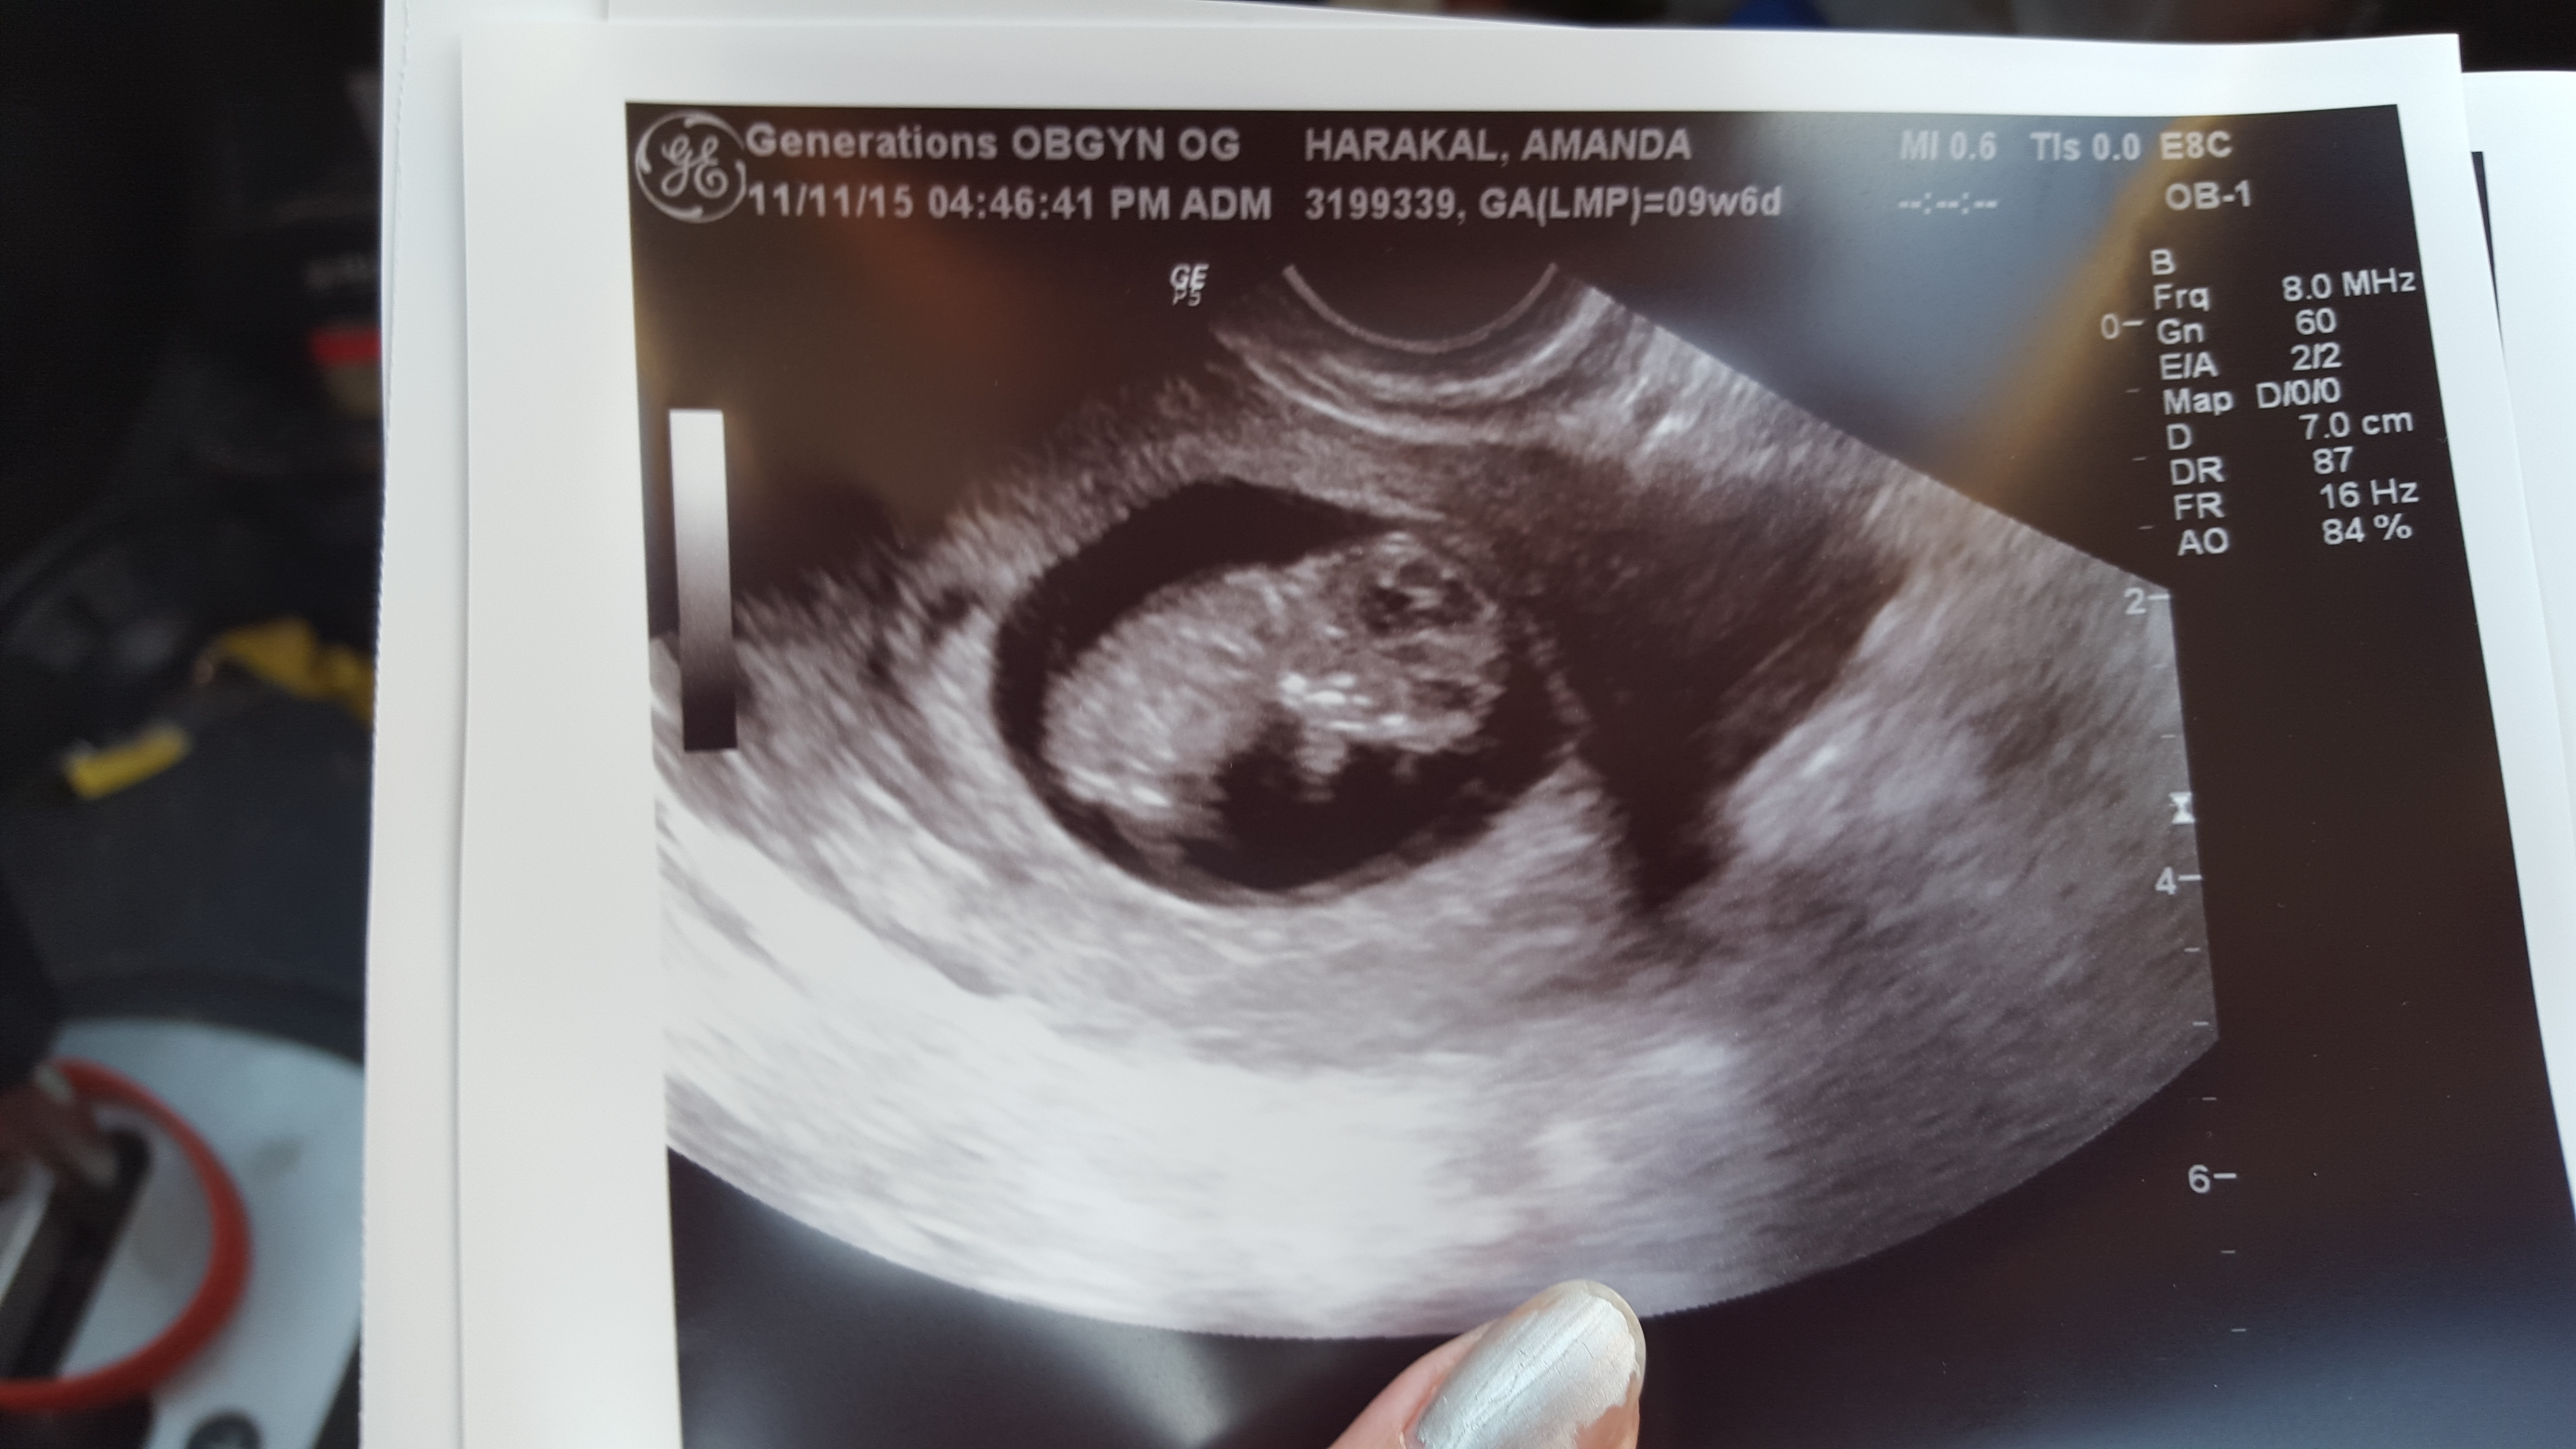

Had our first scan today at 9w5d HB 178!! My OB had trouble with the machine so the measurement is a little smaller than what baby really is, going for NT scan in a few weeks